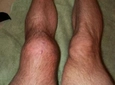

Bu ameliyattan sonra diz kapağımın üzerine basmaktan korkuyorum, diğer bacağıma da aynı şekilde yük bineceğinden endişeliyim. Ameliyat sonrasında bu durumu nasıl yönetebilirim?

Geçmiş olsun dileklerimi iletmek isterim öncelikle. Ameliyat sonrası yaşadığın korku ve endişeler son derece normal. Bu durumu yönetebilmek için, ilk olarak doktorunun tavsiyelerine ve verdikleri rehabilitasyon programına harfiyen uymanı öneririm. Fizyoterapist ile çalışmak, diz kapağına binecek yükü ve diğer bacakta oluşabilecek problemi minimize etmek açısından önemlidir. Ayrıca, yürürken ya da hareket ederken destekleyici aparatlar kullanmak da başlangıçta yardımcı olabilir. Psikolojik olarak ise, bu sürecin zamanla iyileşeceğini ve sabırlı olmanın önemini unutmamalısın.